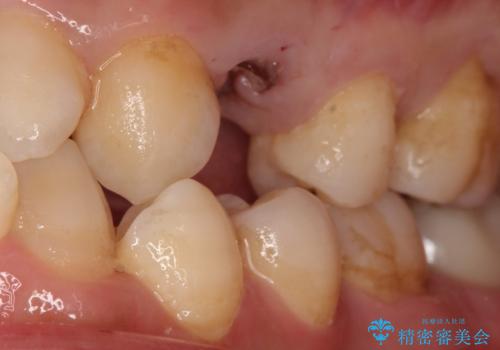

虫歯がかなり進行していて根っこしか残っていない状態でした。日々の歯ブラシが上手く出来ていなくプラーク(細菌の塊)も溜まっている状態でした。

歯を保存するのは出来ないと診断し抜歯した後にインプラントで治療を行いました。

長い間虫歯を放置していたため、根っこだけになっている状態でした。このままでは被せ物を被せられないため抜歯を行い治癒を待った後にインプラントを埋入しオールセラミッククラウンで治療を行いました。